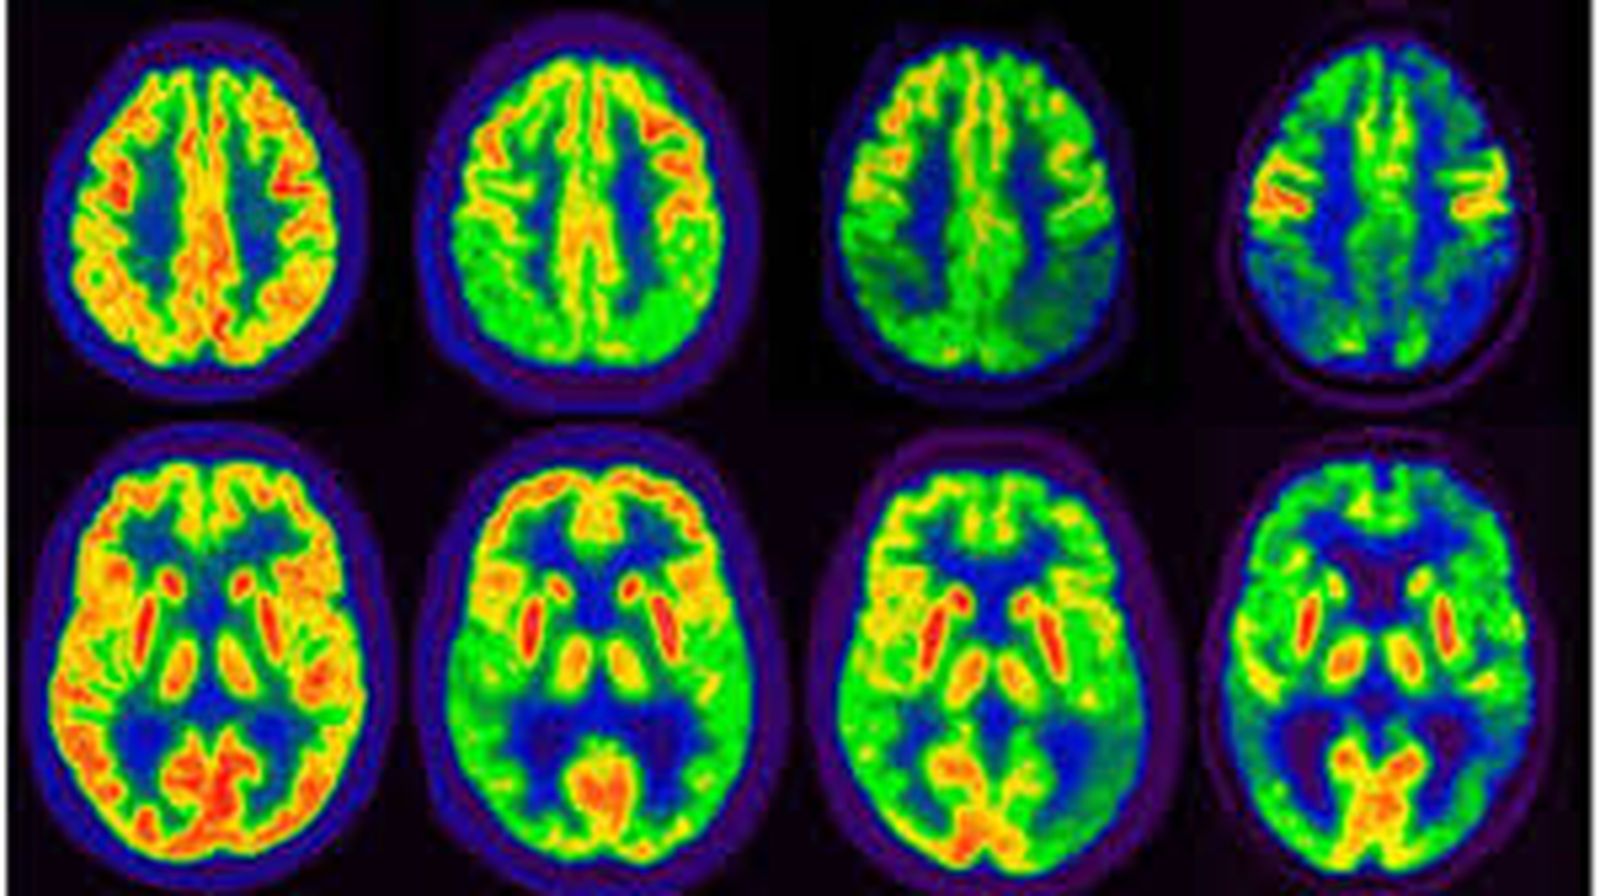

Aunque sea a salto de mata, no quisiera dejar pasar este día sin atraer un momento la atención de los seguidores de este blog sobre “otra peste”, de la que hoy se habla mucho menos que de la Covid-19 y cuya persistencia en el tiempo y en los medios ha reducido prácticamente a una rutina molesta más de nuestras vidas hasta el punto de que, de no estar directamente afectados por ella, preferimos orillar o pasar de puntillas por su escenario. Me estoy refiriendo a que hoy se celebra el “día mundial del alzhéimer”, la enfermedad neuronal degenerativa que lentamente va reduciendo a polvo la condición humana, en lo espiritual y en lo físico, no solo de los pacientes, sino también de muchos de sus cuidadores.

En estos momentos, en España cabe hablar de más de ochocientos mil enfermos de alzhéimer y de, por lo menos, dos millones más de personas afectadas como cuidadores principales o de apoyo. Así, ¡casi tres millones de españoles se las ven todos los días con esta danza macabra de la condición humana, muy agravada por la longevidad que hoy ya alcanzamos, desorientados frente a un fenómeno que mata mucho antes de que el enfermo muera y que sume en la más absoluta impotencia a cuantos se mueven a su alrededor! Aunque a nada conduzcan las comparaciones por lo de que a cada palo le toca aguantar su vela, lo cierto es que, para darnos cuenta a fondo de este drama, basta pensar que se trata de una peste muy similar a la mencionada del coronavirus, la pandemia que nos acongojó de tal manera que pudimos aguantar, no solo sin rechistar, sino también aplaudiendo, largos meses confinados en angosturas a veces más atosigantes que los muros de una cárcel. Digamos, para abundar en los rasgos más dramáticos de la tragedia, que mientras el grueso de esta peste parece que podrá dilucidarse o diluirse, como estamos viendo, en un par de años, la del alzhéimer corroe el cuerpo del enfermo y el espíritu de su cuidador a veces durante un porrón de años.

Ambas afectan a un número parecido de españoles, aunque una desencadene una pandemia producida por contagio y la otra sea una enfermedad neurodegenerativa que no contagia más que piedad y ternura. Ninguna de ellas mata directamente de por sí, sino por otras patologías del enfermo. De hecho, un porcentaje importante de los afectados por la Covid-19 ni siquiera llega a tener síntomas y la afección solo dura unos días, si bien, cuando prende a fondo y mete en danza el sistema respiratorio, el drama dantesco que origina se hace insoportable. El alzhéimer, en cambio, desencadena una acción lenta y desesperante durante la que parece que el enfermo va bebiendo la muerte a pequeños sorbos. Así, día a día, salvo que otra patología le salga al paso y se lo lleve por delante, el enfermo va perdiendo muy poquito a poco los contornos y la estructura misma de su humanidad, forzando con ello el crecimiento salvador de humanitarismo en cuantos se mueven en torno a él. ¡Cuanta más humanidad pierde el enfermo, más humanos han de ser sus cuidadores!